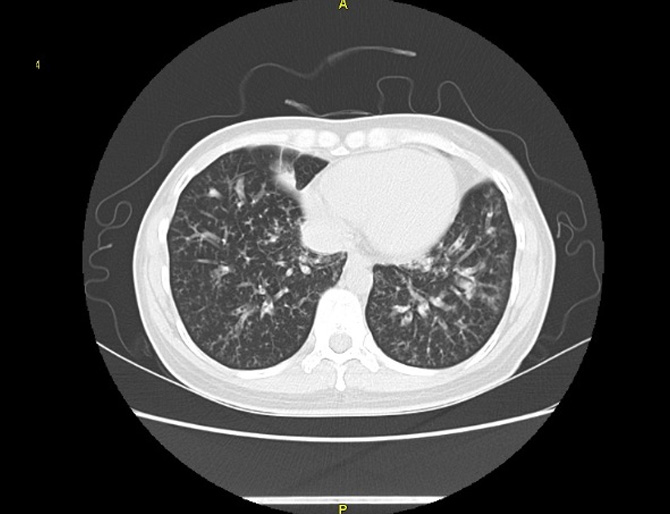

기관지확장증의 CT 사진

비결핵항산균에 감염된 폐사진